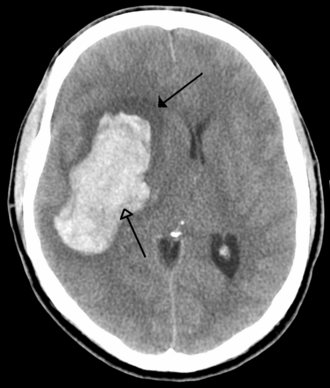

Intracerebralno krvarenje

Obično se javlja u malim arterijama ili arteriolama i najčešće nastaje zbog povišenog krvnog tlaka[24], vaskularnih malformacija središnjeg živčanog sustava (uključujući kavernozne angiome ili arterijskovenske malformacije), cerebralne amiloidne angiopatije ili infarkta u kojima se sekundarno razvilo krvarenje[2]. Drugi potencijalni uzroci su trauma, poremećaji koagulacije, amiloidne angiopatije, komzumiranje droge (npr. amfetamini ili kokain). Hematom se povećava sve dok pritisak okolnog tkiva ne ograniči njegov rast ili ne dođe do dekompresije pražnjenjem u cerebralni ventrikularni sustav, cerebrospinalnu tekućinu ili pialnu površinu. Trećina intrecerebralnog krvarenja je krvarenje u moždane komore. Intracerebralno krvarenje ima smrtnost od 44% nakon 30 dana, višu od ishemijskog moždang udara ili subarahnoidalnog krvarenja (koji e tehnički mogu klasificirati kao vrsta moždanog udara)[2].